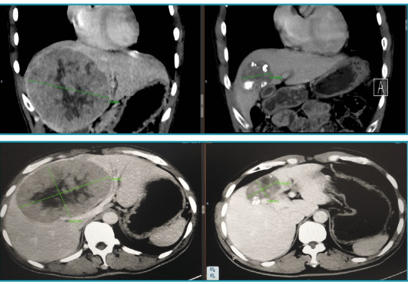

肝脏肿瘤介入载药微球栓塞、消融后肿瘤明显坏死